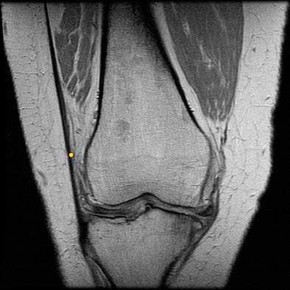

Question 2

A 22-year-old elite soccer player undergoes an anterior cruciate ligament (ACL) reconstruction. Preoperatively, she demonstrated a high-grade pivot shift test. The surgeon decides to perform an anterolateral ligament (ALL) reconstruction concurrently to improve rotational stability. Which of the following is true regarding the anatomy and biomechanics of the ALL?

Explanation

The anterolateral ligament (ALL) originates posterior and proximal to the lateral femoral epicondyle and inserts on the proximal tibia midway between Gerdy's tubercle and the fibular head. It acts as a secondary restraint to internal tibial rotation and the pivot shift phenomenon.